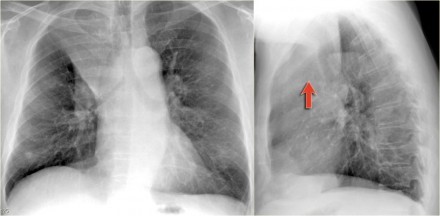

肺不张胸片,肺不张胸片表现

胸疾病胸片表现之肺不张

肺不张胸片表现

肺不张x线表现

肺不张胸片典型图片

肺不张胸片表现图片